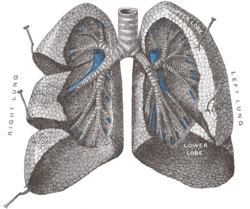

Plíce savců jsou párové orgány uložené v hrudní dutině. Na povrchu jsou hladké, zdravé plíce jsou narůžovělé. Jejich barva svědčí o prostředí, ve kterém pracovaly, plíce lidí (ale i psů), kteří žijí ve městech, jsou zašedlé, plíce kuřáků jsou černé, na jejich povrchu jsou vidět dehtové skvrny. Plíce mají houbovitou konzistenci. Už po prvním nádechu se naplní vzduchem, část tohoto vzduchu už se nikdy nedostane z plic ven. Proto plíce živě narozených dětí (i mláďat ostatních savců) ve vodě plavou, na rozdíl od plic mrtvě narozených, které klesnou ke dnu. Této skutečnosti se využívá v soudním lékařství. Hrudní dutina je vystlána pleurou, tenkou vazivovou blánou. Pleura, která pokrývá hrudní stěnu, se nazývá pohrudnice (parietální pleura). Pleura přechází na plíce a pokrývá je jako poplicnice (viscerální pleura). Mezi pohrudnicí a poplicnicí je úzký prostor, zbytek tělní dutiny coelomu, který je vyplněn malým množstvím tekutiny, která umožňuje hladký pohyb. V pohrudniční dutině je také podtlak, který zabraňuje kolapsu měkkých plic a umožňuje jejich naplnění vzduchem při nádechu. Při proděravění pohrudnice se tlaky v pleurální dutině vyrovnají a plíce zkolabuje. Tento stav se nazývá pneumothorax. Mezi plícemi je pleurou obalený prostor, středohrudí, ve kterém je uloženo srdce a ve kterém probíhají důležité cévy, nervy a jícen.

Stavba plic

Každá plíce má zhruba trojúhelníkovitý tvar, levá plíce je menší než pravá. Plicní základna (basis) se dotýká hlavního dýchacího svalu savců, bránice. Plicní hrot (apex) směřuje směrem k hlavě. V plicní brance (hilus) do plíce vstupuje prudůška (bronchus), plicní žíly a plicní tepna, mízní žíly a nervy. Na vnitřní ploše plic jsou otisky orgánů středohrudí, hlavně srdce. Plíce jsou rozčleněné na laloky, u člověka má pravá plíce laloky tři, menší levá má dva. Třetí lalok pravé plíce, lalok přídatný (lobus accessorius) se vsouvá do prostoru mezi velkými žílami a srdcem, u člověka má jazýčkovitý tvar, proto se mu také říká lingula, jazýček. V průměrných plicích se udrží okolo 3 litrů vzduchu.[1] Každý lalok je dále rozdělen vazivovými přepážkami, které vycházejí z poplicnice, na bronchopulmonální segmenty. Každý segment má vlastní přívod vzduchu i krvení. Segmenty jsou dále rozděleny na lalůčky, aciny, které mají pyramidový tvar. Základna acinu je na povrchu plíce, hrot směřuje k plicní brance. Vnitřek plic se skládá z rozvětvujících se prudůšek, tedy dolních cest dýchacích, a dýchacího oddílu, části, kde dochází k výměně plynů. Prudůška, která vstupuje do plic plicní brankou, se 25krát větví (u člověka). Tvoří tak prudůškový strom (arbor bronchalis) Hlavní prudůška (bronchus principalis) → lalokové prudůšky (bronchi lobares) → segmentální prudůšky (bronchi segmentales) → subsegmentální prudůšky → terminální prudůšky V průběhu větvení se mění stavba stěny prudůšek, hlavní prudůška má podobnou stavbu stěny jako prudůšnice, je tvořena chrupavkou, s každým dalším větvením chrupavky ubývá a relativně přibývá hladké svaloviny. Sliznice je pokrytá řasinkovým epitelem, řasinky kmitají směrem ven a pomáhají odstraňovat nečistoty. V průběhu větvení časem zmizí i hladká svalovina, stěna je tvořena jen tenkou sliznicí, s epitelem s řasinkovými buňkami, malým množstvím pohárkových buněk a buňkami Clarovými, které produkují sufraktant, látku, která snižuje povrchové napětí a brání tak kolapsu prudůšky. Jedna terminální prudůška ventiluje jeden plicní lalůček. V něm se větví na prudůšinky (bronchioli), které už patří k dýchacímu oddílu plic. Průdušinky se několikrát rozvětví, až na respirační prudůšinky (bronchioli respiratorii). Tyto prudůšinky ústí do plicních sklípků, alveolů. Každý respirační bronchiolus zásobuje vzduchem asi 200 alveolů.